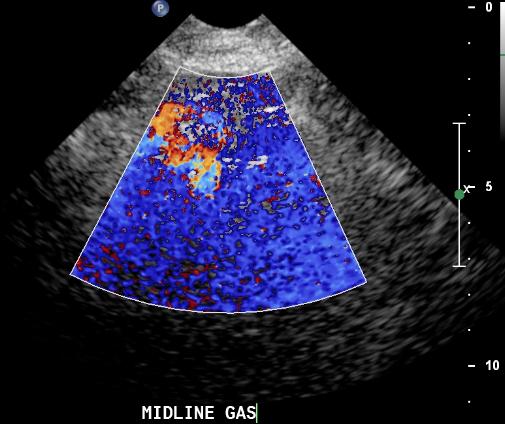

Bowel gas creates a typical artifact both in B-mode and in color flow mode. In B-mode bowel gas artifact looks like flashing lines that tend to obscure anatomical structures. In color flow mode bowel gas creates a disturbing array of random pixels that make it impossible to sample anything under them.

Bowel gas ultrasound artifact

Two things that can be done by the operator to try and limit the effect of bowel gas on the quality of images in renal artery ultrasound include increasing the PRF (color scale) and narrowing the field of vision. Increasing the color scale will bring out quick flowing blood and attenuate the color bruit from gas. Narrowing the field of vision will allow the duplex machine to focus more energy and real-time images on the area of interest.